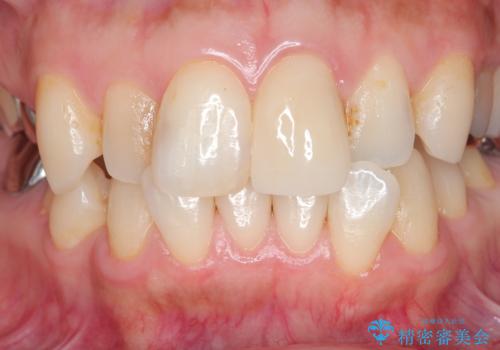

- 自転車で転倒してしまい、前歯を折ってしまい、痛みと見た目の改善を希望され来院されました。

もともと根管治療の為されて歯が折れてしまっているので、根管治療を行い審美的なセラミック治療を行う治療計画としました。

- 15.4万円(ジルコニアクラウン・仮歯・ファイバーコア)費用は治療当時の料金となります

周囲の歯と調和した審美的な仕上がりに満足いただくことができました。